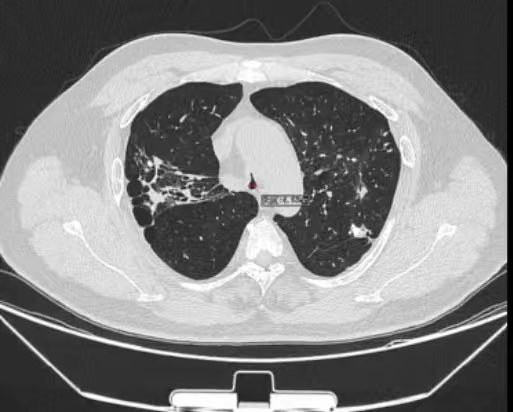

术后医学影像图

术中,麻醉团队在患者气道条件较差的情况下,顺利完成全身麻醉与气道管理,为后续操作提供安全保障。在硬质支气管镜的引导下,手术团队先对狭窄部位进行球囊扩张,随后将术前根据患者的三维CT(计算机层析成像)数据定制的Y型硅酮支架精准地覆盖于气管狭窄段。该支架与患者的气道解剖结构完美贴合,实现最佳支撑效果,并可最大限度地减少黏膜刺激增生等。支架展开后,可稳定地支撑隆突及双侧主支气管,使气道狭窄立即解除。

术后,赵先生自觉呼吸顺畅。复查显示支架位置良好,气道通畅,呼吸困难症状显著缓解。